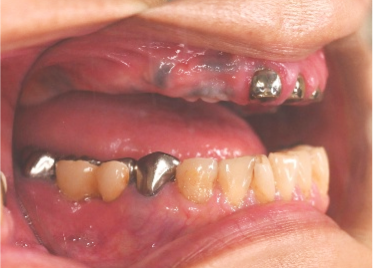

Before

赤丸は抜歯しました。上4本、下3本

After

【義歯を装着したところ】

【義歯を外したところ】